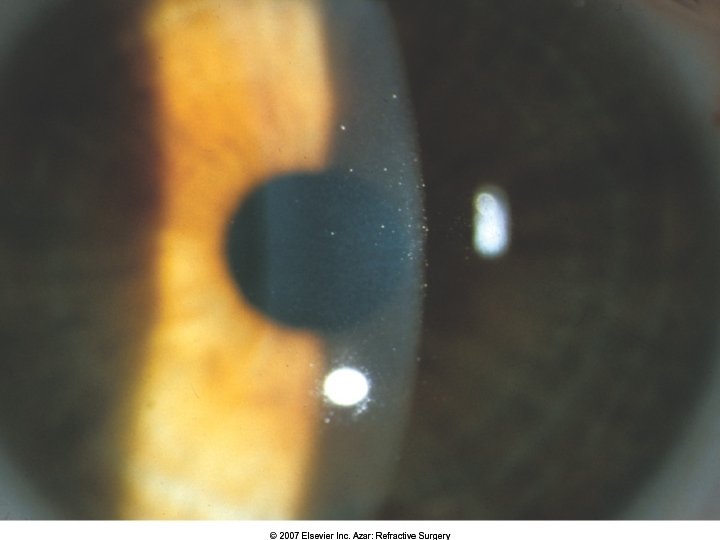

Epithelial ingrowth Commonly noted at flap edge Grows centrally and/or circumferentially from epithelial-interface tract Can present as island “planted” during surgery Dangers: – – Blocking visual axis Blocking nutrition from reaching the flap --> flap necrosis Can occur with enhancement procedures

Epithelial Ingrowth: predisposing factors Inverted flap edge Epithelial defect at flap edge ABMD Flap buttonhole (microkeratome) Free cap (microkeratome) Flap dehiscence Enhancements Hyperopic ablations (larger OZ -- ablates outside stromal bed Older pts

Epithelial ingrowth: Prevention Bandage CL Replace epithelial tags during enhancements Enlarge flaps for hyperopic treatment

Epithelial ingrowth: management Mark ingrowth area and score side-cut with sinskey hook Lift flap under the microscope Use a Tooke knife or blade to scrape epithelial cells off stromal bed Flip flap over and irrigate interface Consider BCL